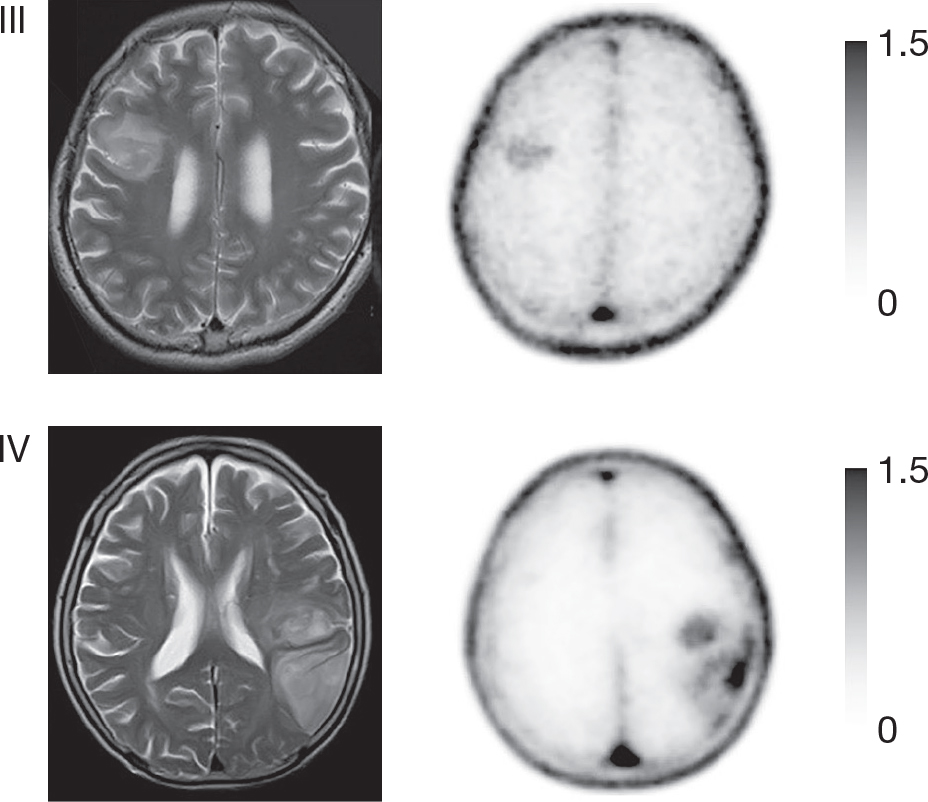

Figure 4. T1-weighted post-contrast (A), FLAIR (fluid-attenuated inversion recovery; B), 11C-MET PET (C) and 18F-FACBC PET (D) images of a patient with diffuse astrocytoma, WHO grade II, IDH mutated. The conventional MR images show a poorly enhancing lesion with some high signal surrounding the lesion. Although increased PET agent uptake can be seen in a small part of the tumor on both the 11C-MET and 18F-FACBC PET images, this case also illustrates the relatively high uptake of the natural amino acid-based 11C-MET in the healthy brain parenchyma compared to the unnatural amino-acid based 18F-FACBC which can result in decreased T/N ratios. This figure is reproduced – with new figure legend appropriate for current book chapter – from Tsuyuguchi et al. (2017), Figure 1 Case 1, under the terms of the Creative Commons Attribution License (http://creativecommons.org/licenses/by/3.0) (80).